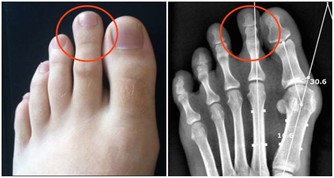

男性的陰囊伸縮性大,分泌汗液較多,加之陰部通風差,容易藏污納垢,局部細菌常會乘虛而入。

這樣就會導致前列腺炎、前列腺肥大、男性性功能下降。

因此,堅持,是預防前列腺炎的一個重要環節。